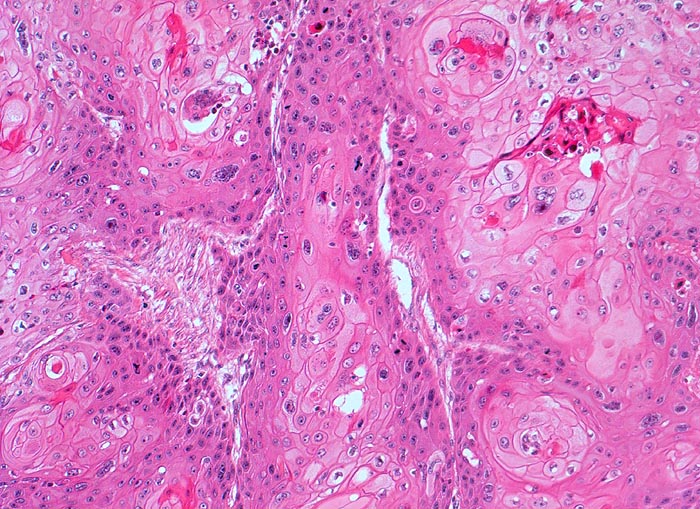

Verhornendes Plattenepithelkarzinom

Harnblase

Solide plattenepithelial differenzierte Tumorzellstränge. Einige Tumorzellnester zeigen im Zentrum Verhornungszeichen. Zahlreiche Mitosen. Tumorzellen mit ausgeprägter Zellkernpolymorphie und reichlich eosinophilem Zytoplasma. Deutliche Zellgrenzen.

Plattenepithelkarzinome treten als Folge chronischer Entzündungen auf. (Dauerkatheterträger, Zyklophosphamid Langzeittherapie mit Zystitis, Bilharziose).